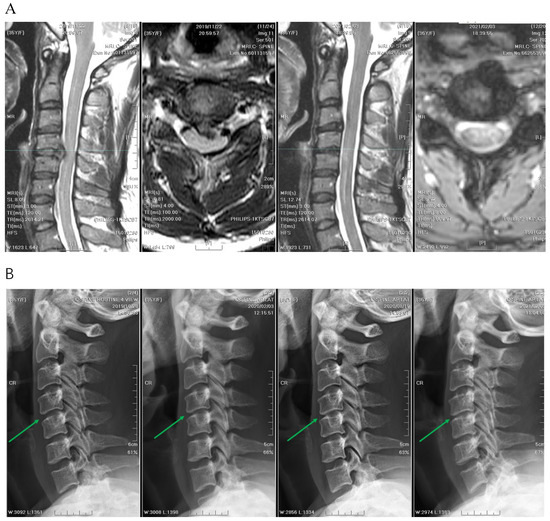

2. Materials and Methods

2.1. Patient Information

2.2. Patient Selection

2.3. Clinical and Radiological Parameters

2.4. Preoperative Workup, Positioning, and Operative Technique

2.5. APECD

2.6. PPECD

3.4. Radiographic Outcomes